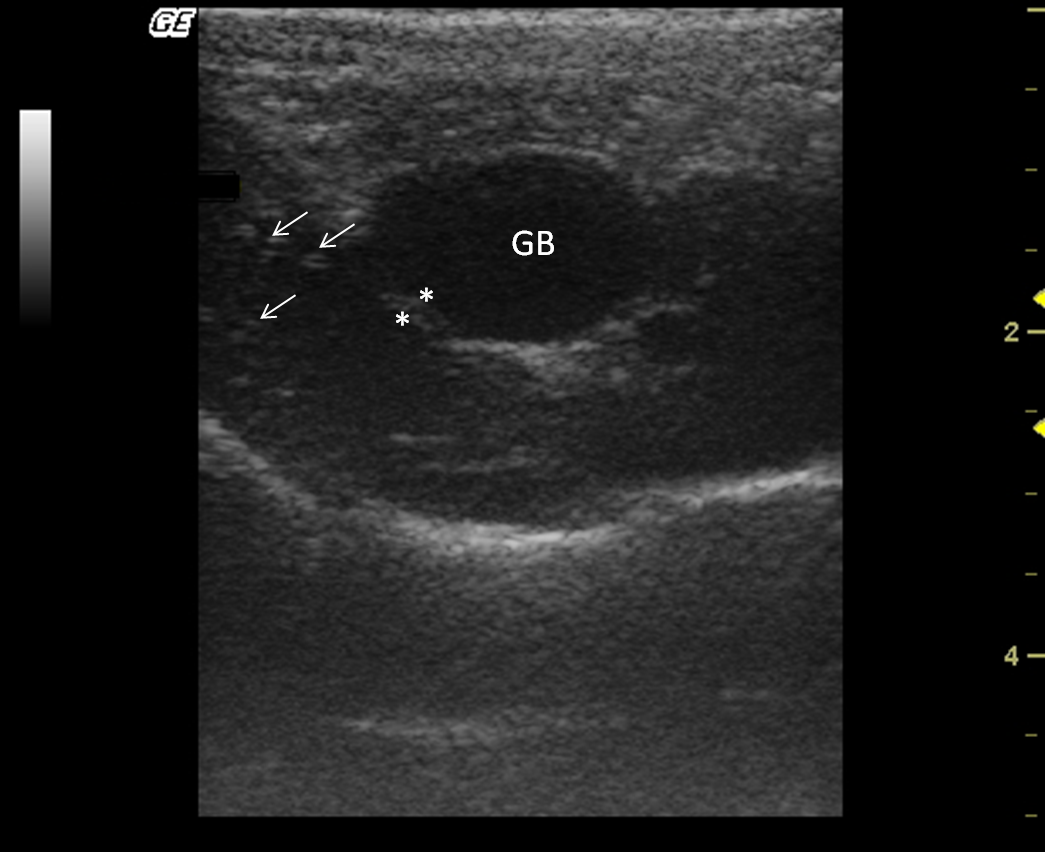

The liver size was assessed subjectively; it was located entirely within the rib cage, cranial to the stomach in all monkeys. All howler monkeys had liver parenchyma with homogeneous hypoechogenic echotexture compared with the cortex of the right kidney. Liver parenchyma also showed hyperechoic portal vessels walls (Fig. 4). The presence of gas in the stomach made it difficult to visualize the liver completely in two males.

|

Figure 4. Transverse sonogram of the liver in an Alouatta fusca. The liver parenchyma presents a hypoechogenic ecotexture with hyperechogenic portal vessels walls, with the appearance of a “starry sky”. The gallbladder is filled with a homogeneous anechoic content, has a hyperechoic wall when compared with the hepatic parenchyma. |

The gallbladder had homogeneous anechoic fluid content; luminal debris was not detected. The gallbladder wall was totally or partially visualized as a hyperechoic line when compared with the hepatic parenchyma, average measuring 1.5 mm thick. Post-mortem studies allowed identification of liver lobes: papillary process of the caudate lobe, caudate process of the caudate lobe, left lobe, quadrate lobe and right lobe; this allowed for a comparison of ultrasound imaging and anatomic position (Fig. 5).

Figure 5. Post-mortem preparation of Alouatta fusca liver (anterior view), showing the disposition of the gallbladder (GB) and hepatic lobes: (1a) papillary process of the caudate lobe, (1b) caudate process of the caudate lobe, (2) left lobe, (3) quadrate lobe, (4) right lobe. |